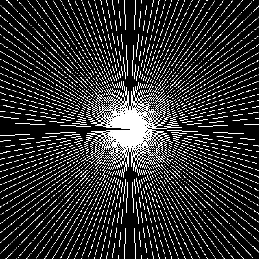

Where x is denoted as the MRI to be reconstructed, y are the k-space data, and Fusubscript𝐹𝑢{F_{u}} represents the under-sampled Fourier encoding matrix. The first term Fuxy22superscriptsubscriptnormsubscript𝐹𝑢xy22{\|{F_{u}}\emph{x}-\emph{y}\|}_{2}^{2} indicates data fidelity that can ensure the consistence between the Fourier coefficients of the reconstructed image and measured data. The second term Risubscript𝑅𝑖{R_{i}} is an analytical, sparsifying transform term, and αisubscript𝛼𝑖{\alpha_{i}} is a factor for balancing data fidelity and transform terms. MR images can be generated by inverse Fourier transform of the sampled k-space data, which are the Fourier coefficient of an object. However, aliasing artifacts (noise-like) are produced by the incoherence of under-sampled k-space in transform domain, as shown in Fig. 1.

Figure 1: The zero-filled reconstruction. (a) is a full-sampled MRI, (b) is a 20% radial sampling mask, (c) is the zero-filled reconstruction under (b), and (d) is the reconstruction using our method. Note that aliasing artifacts are clearly seen in the zero-filled reconstruction (c), which impair diagnostic information. However, our algorithm can remove these unpleasant artifacts (d).